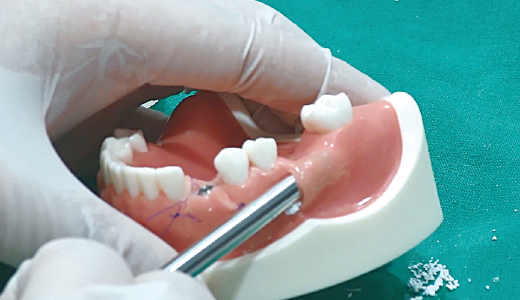

임플란트에 CowellBMP 코팅 시 : CowellBMP 용액을 원형 홈에 3~4방울 떨어트려서 임플란트에 코팅

1. Bone Carrier의 원형 홈에 먼저 rhBMP-2 용액을 주사

2. Hand-piece를 이용하여 원형 홈에 Fixture를 천천히 회전